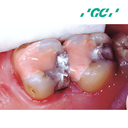

Fuji 7

Fluoride-releasing Light Curable Glass Ionomer Cement